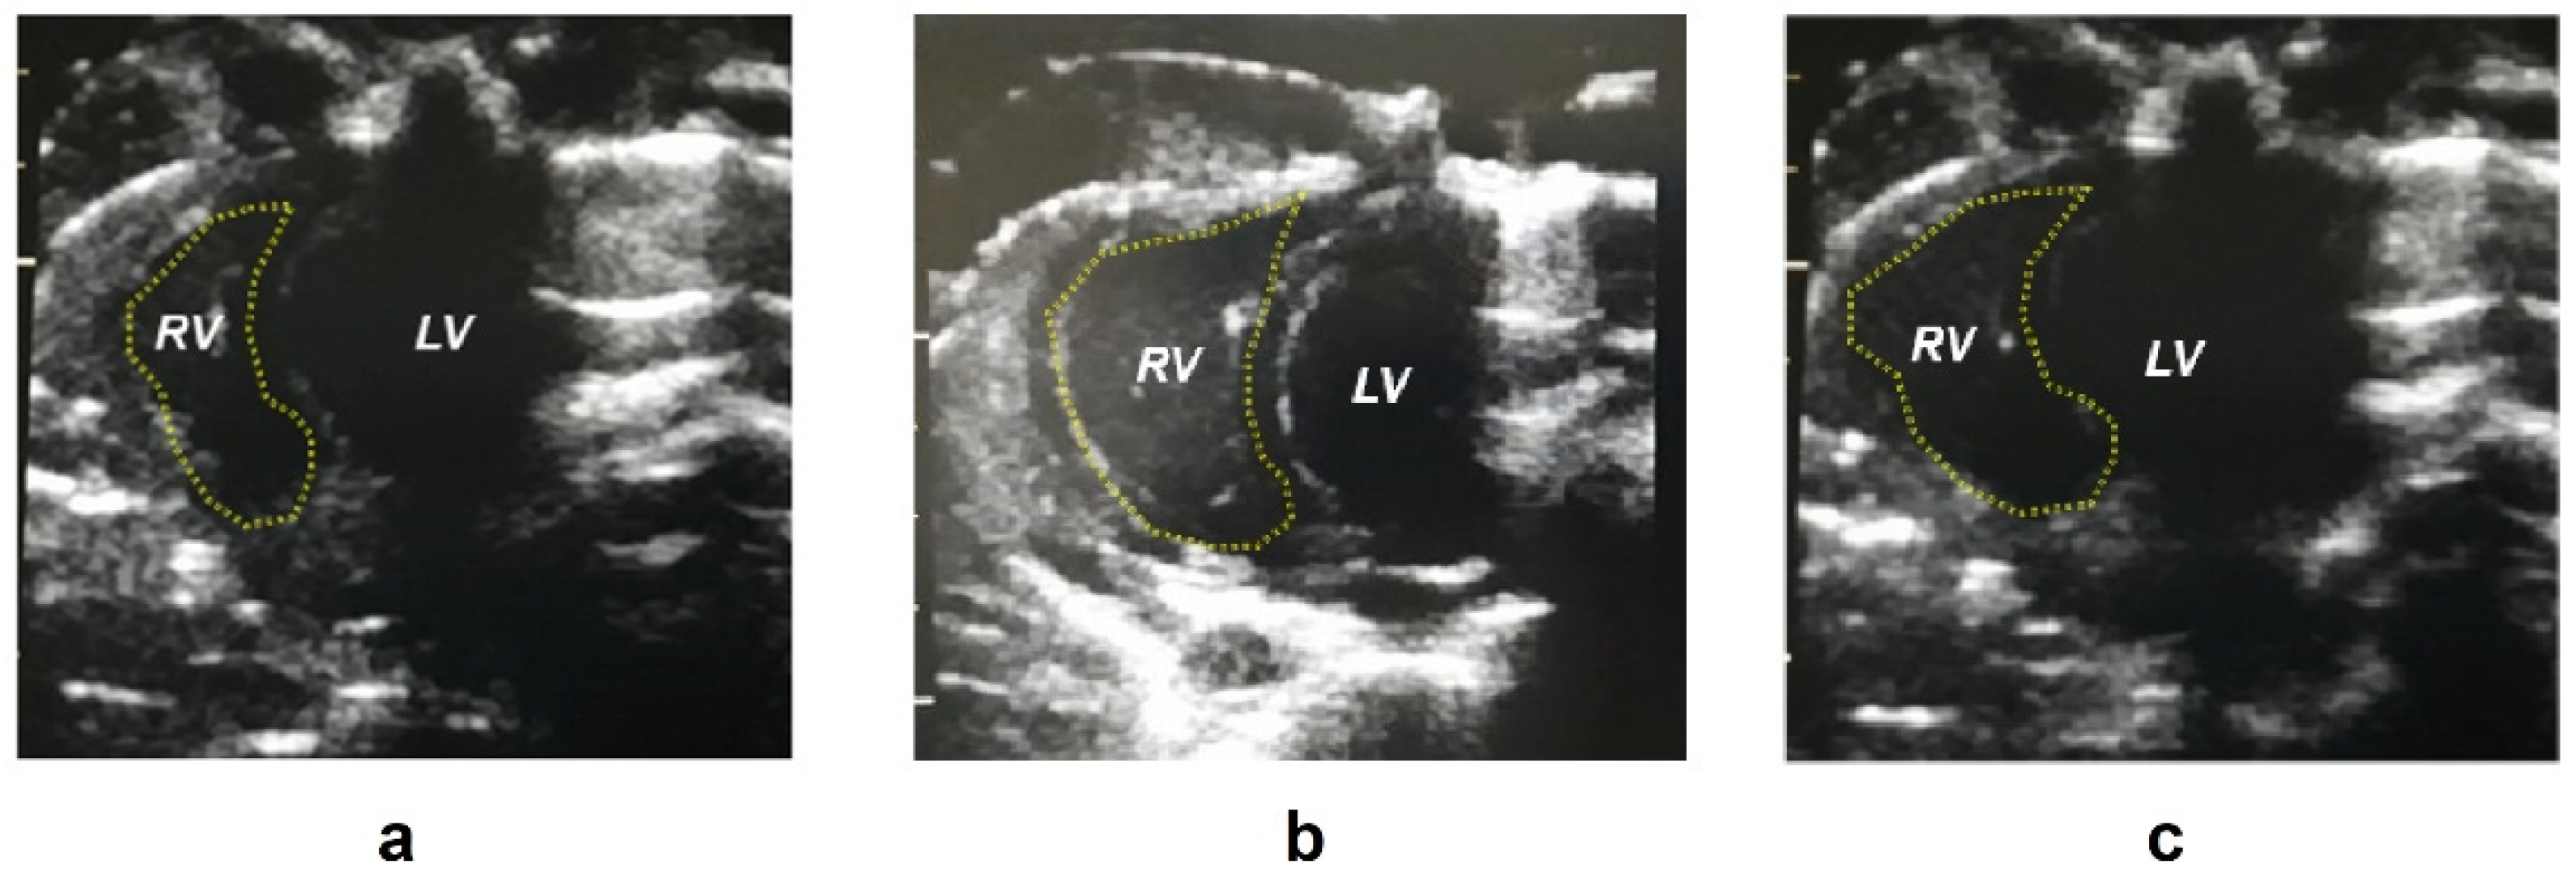

| Right ventricle area d (mm2) | 28.0 ± 5.26 **** | 48.3 ± 5.77 | 44.3 ± 7.55 |